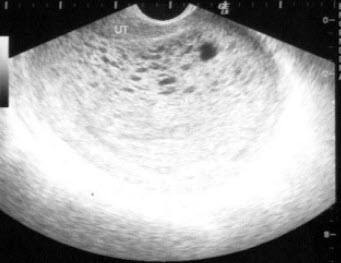

②阴式B超图片更清晰,结果更准确。以多囊卵巢为例,即使不是专业医生,也能知道卵巢中有多个成熟而未排出的卵子。